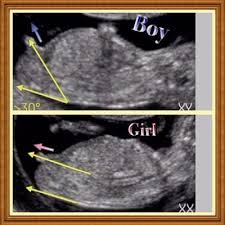

نظرية رامزي لتحديد جنس الجنين

شكل الجنين في الشهر الثالث بالسونار ولد و بنت المرسال

كيف اعرف نوع الجنين من ورقة السونار 3a2ilati